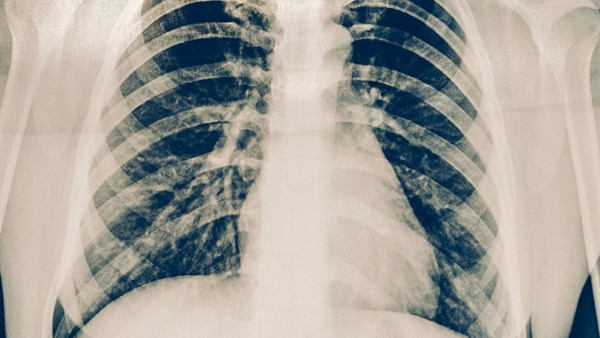

布洛芬被公认为“最安全”的解热镇痛药之一,广泛应用于世界各地的止痛和感冒药中。但最近,布洛芬被质疑有加重新冠肺炎病情的风险。最近一项研究提出的《柳叶刀》假设说,服用布洛芬等止痛抗炎药后,一种酶会得到加强,可能会鼓励和恶化新型冠状病毒感染。